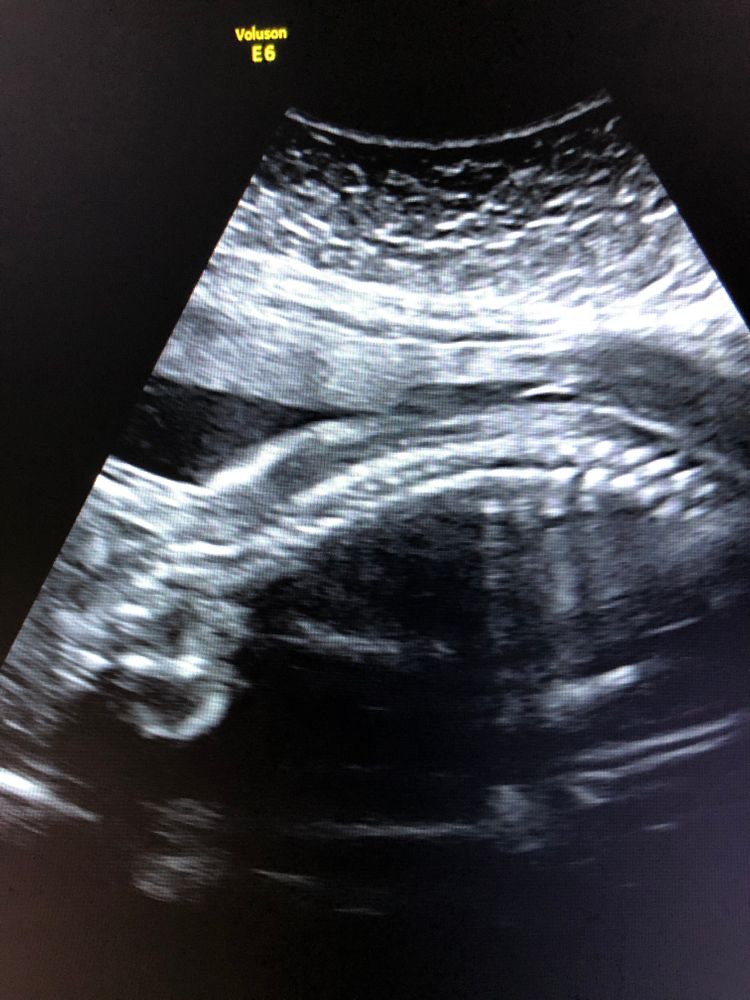

ниже прикреплю снимки абсолютно «нормальных» спинок😌 специально сохранила примерно в таком же положении как у Вас